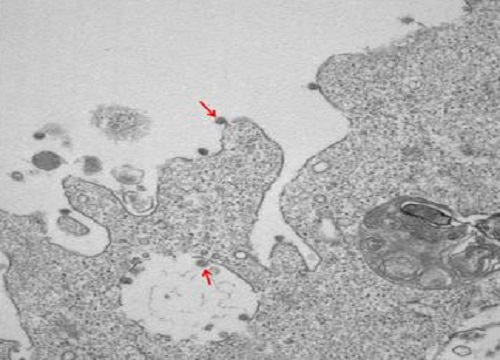

La prima immagine del Virus Lombardo isolato dal gruppo Ospedale Sacco/Università Statale di Milano

Prime immagini al microscopio elettronico del virus SARS-CoV-2 isolato presso il Laboratorio di Malattie Infettive dal gruppo coordinato dai prof. Massimo Galli e Gianguglielmo Zehender, in collaborazione con l’Anatomia Patologica diretta dalla prof.ssa Manuela Nebuloni del Dipartimento di Scienze Biomediche e Cliniche Luigi Sacco dell’Università degli Studi di Milano.

Hanno ottenuto gli isolamenti i ricercatori Alessia Lai, Annalisa Bergna, Arianna Gabrieli e Maciej Tarkowski, mentre hanno effettuato le osservazioni al microscopio elettronico e prodotto le bellissime immagini le dott.sse Antonella Tosoni e Beatrice Marchini.

1. Nella foto si osservano chiaramente, ad un ingrandimento di 30000X, le particelle virali di SARS-CoV-2 (indicate dalle frecce), adese alle membrane sulla superficie e all’interno di cellule VERO E6 utilizzate per l’isolamento.